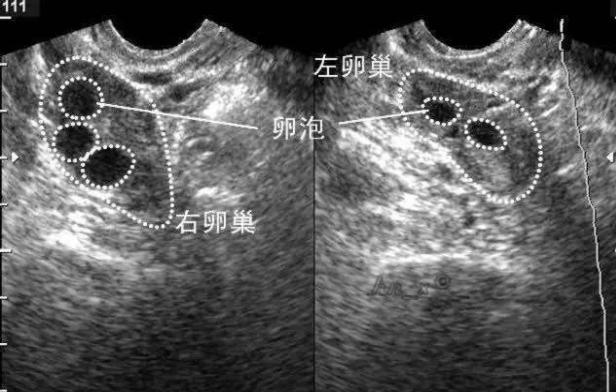

卵泡监测有以下几种方法:1)月经周期推算法;2)基础体温(BBT)测量法;3)排卵试纸检测法;4)宫颈粘液观察法;5)经阴道超声监测排卵。目前,B超是广泛、全面地监测排卵情况的方法。在B超下可以动态地测量卵泡的发育成长和大小,观察卵泡的排卵,观测子宫内膜的厚度和形态,非常精确、方便、无创伤。

●月经3-5天:观察窦状卵泡数量(常用于月经失调的女性)。

●月经9-12天:常规开始监测卵泡,隔2-3天监测。

●当卵泡>15mm时:每天或隔天监测。

●当卵泡>18mm时:为成熟卵泡,此时可根据医生的建议,合理安排诱导卵泡排出,此时同房怀孕就能事半功倍。